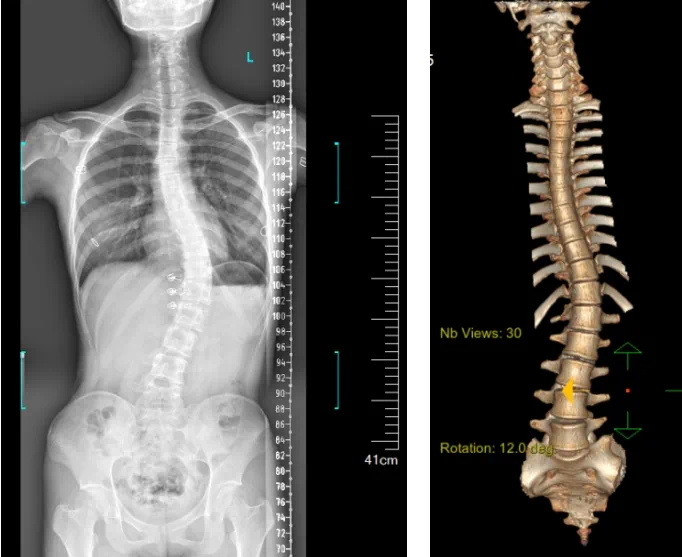

患者為一名16歲女孩,發現脊柱側彎1年,到南方醫院贛州醫院脊柱外科求診。經查體,患者左右胸廓不對稱,雙肩等高,左肩胛骨隆起,背側呈“剃刀背”畸形,胸腰段棘突偏離正中線,胸腰段脊柱左側凸畸形;各棘突無壓痛及叩擊痛,右側腰部凹陷,胸腹及腰背部感覺正常。檢查發現患者特發性脊柱側彎,Lenke5C型,主胸彎51°。患者及家屬對外觀不滿意,為改善外觀及功能,要求手術矯形治療。

據悉脊柱側彎手術治療后可以保持軀干平衡,改善外觀并防止畸形進一步發展?;颊叩纳钯|量得到提高,進而減少脊柱過度畸形可能帶來的疾病的發生率,外觀上的積極變化往往也能帶來患者心理與精神的積極變化。臨床上會綜合考慮患者的年齡、側彎程度、進展趨勢、骨質條件、鄰近節段情況、手術節段等因素,合理采用個性化的手術方式進行治療。然而,由于脊柱神經血管密布,手術操作相對復雜,手術難度高、風險大,傳統脊柱側彎的手術方式往往有較高的神經或脊髓損傷風險。故此次科室決定開展機器人輔助導航下脊柱側彎矯形、植骨融合內固定手術。術前,醫生團隊在機器人多維度圖像融合智能手術規劃功能的輔助下,預先規劃了理想的置釘路徑。術中,天璣骨科手術機器人準確遵循術前規劃,根據配準結果,實時定位并準確執行置釘操作,所有導針均用電鉆置入,一次性成功,協助醫生順利完成手術。最終,在麻醉科、手術室密切配合下,歷時3小時成功完成側彎矯形術,出血量僅500ml。術后,患者恢復良好,大小便及下肢神經運動感覺正常。